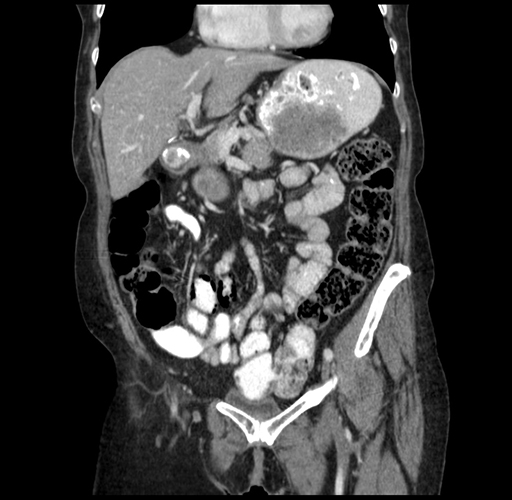

Pre-Chemo: Coronal Venous

Coronal Venous